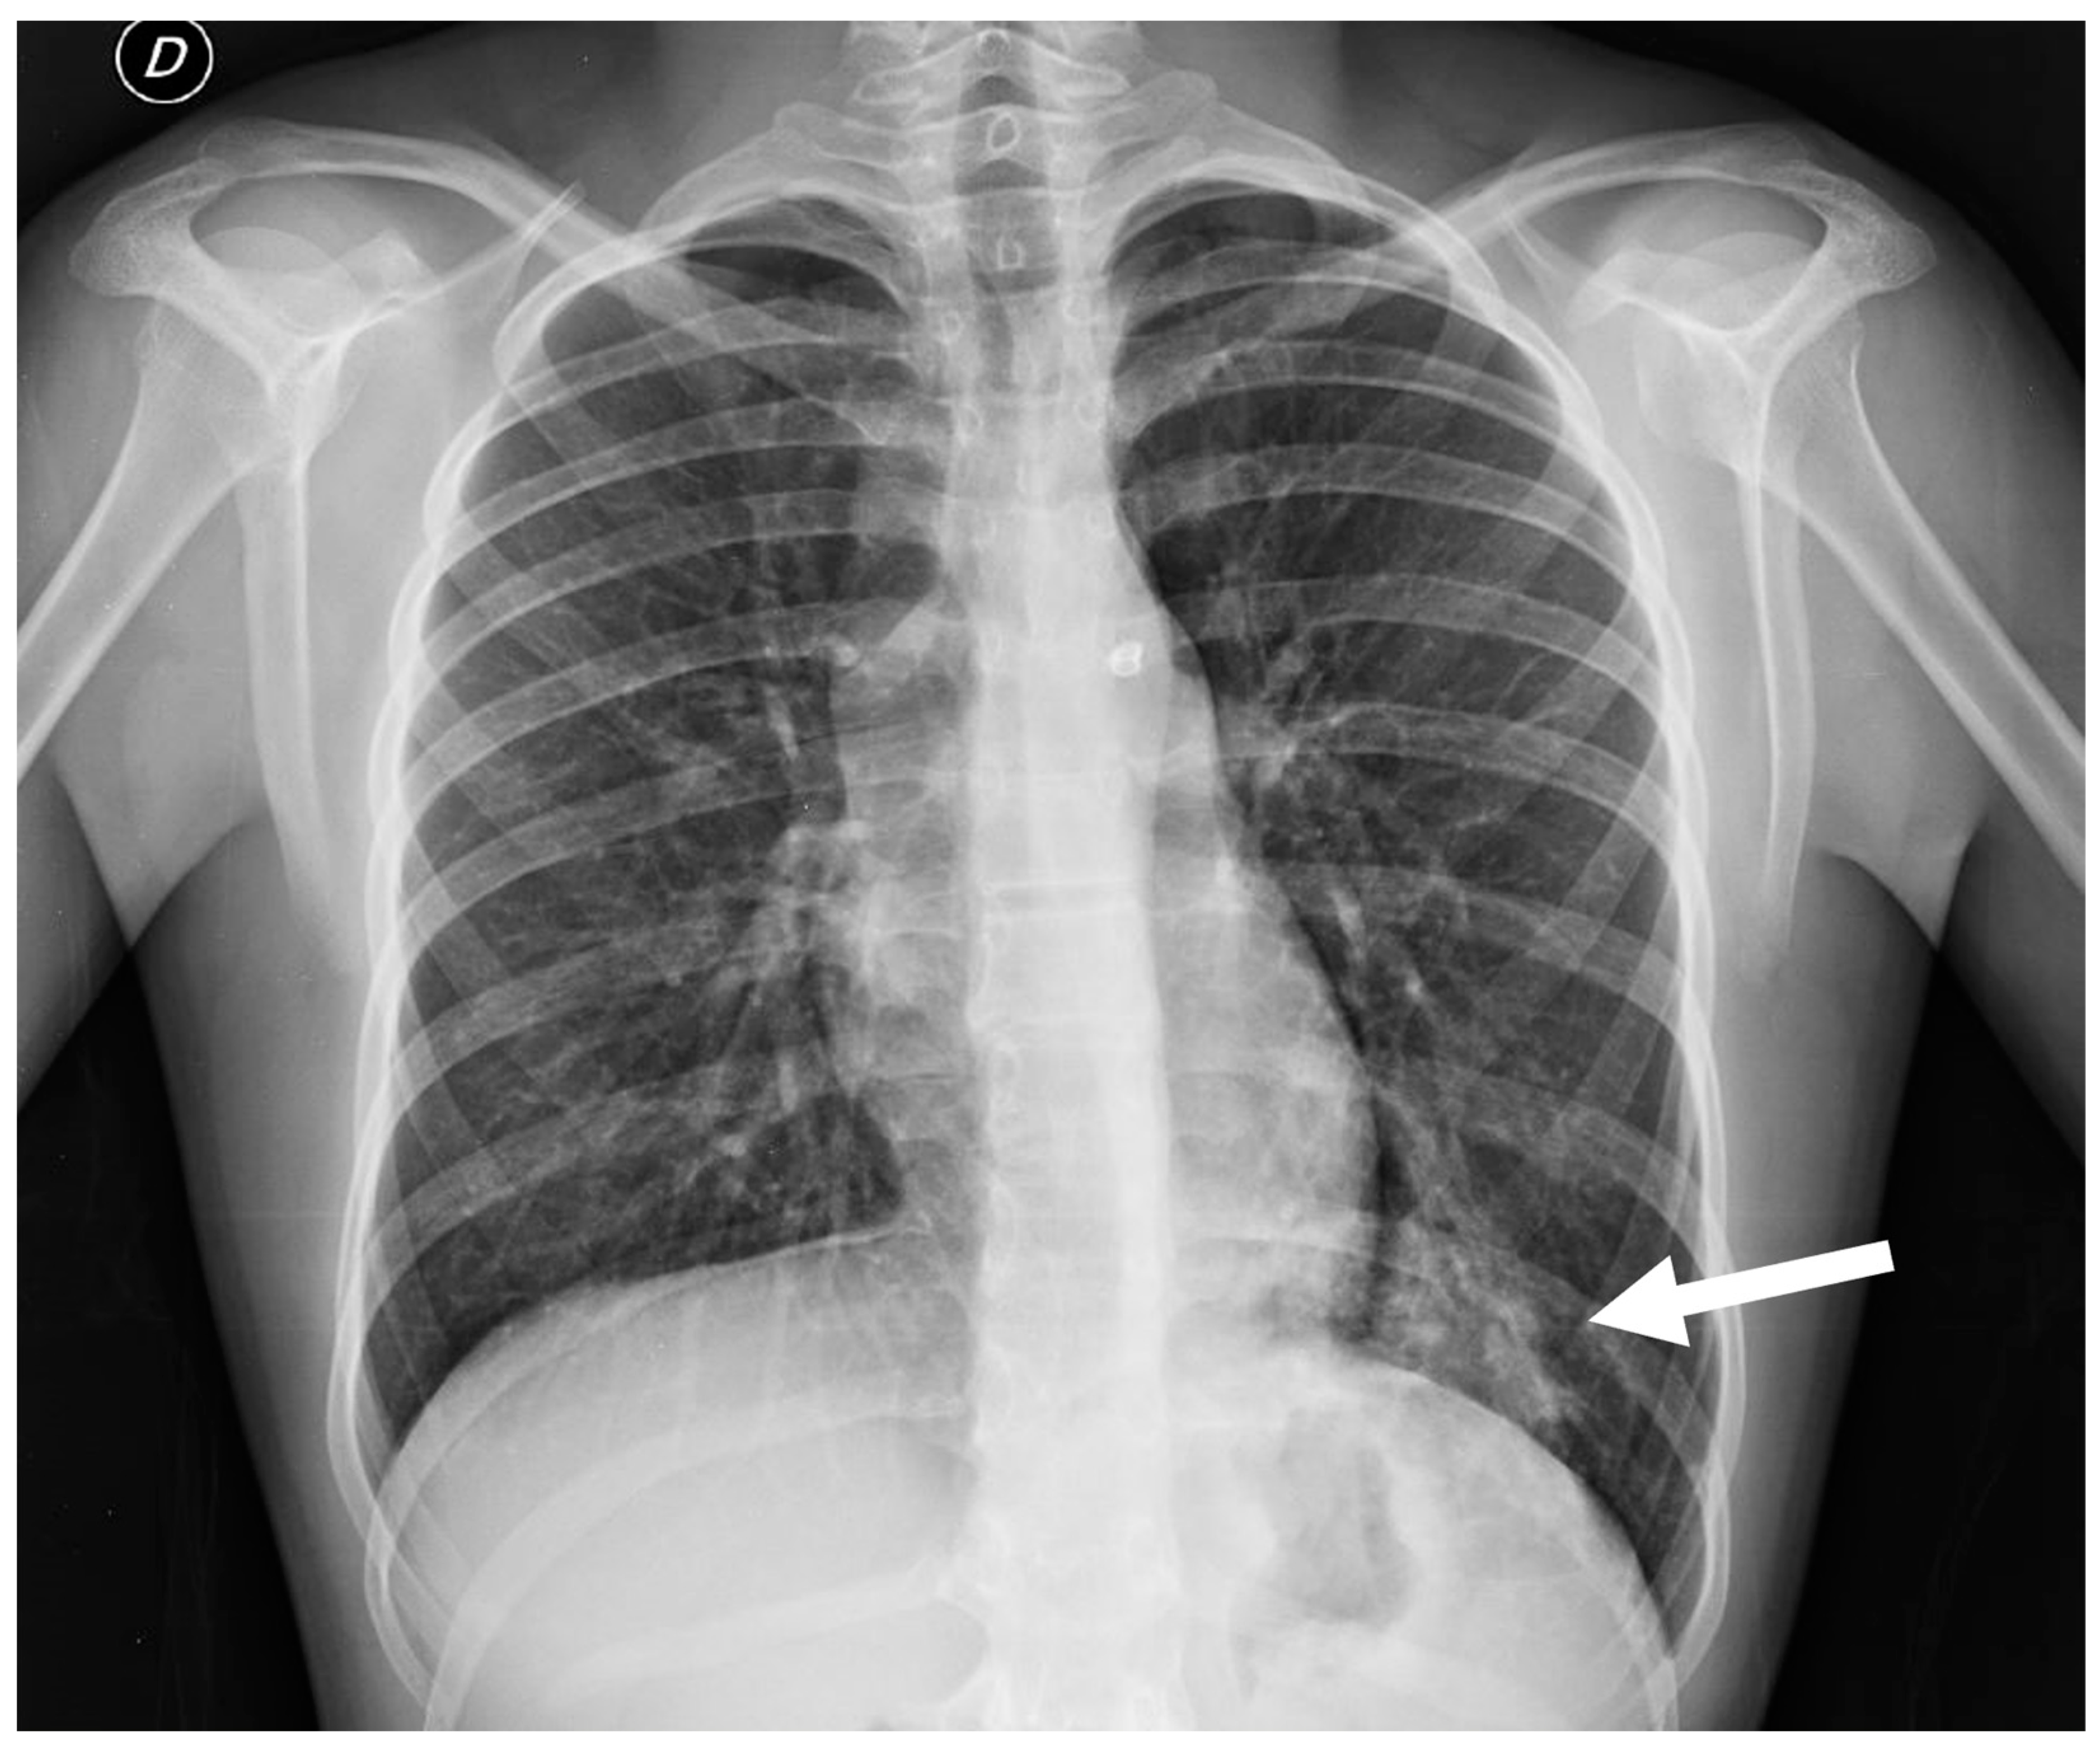

Chest radiography is a valuable initial imaging modality for pulmonary sequestrations. In up to 98% of cases, it demonstrates these malformations as circumscribed lung masses predominantly involving the lower lobes, with a left-sided predilection [15,35]. Additionally, the anomalous systemic arterial supply may sometimes be visualized on plain radiographs [4]. In cases of intra-lobar sequestration, repetitive infections can predispose a patient to liquefaction necrosis, manifesting radiographically as a mainly cystic lesion that may contain air-fluid levels [8,15] (Figure 13).

Figure 13.

Chest radiograph of a 17 year old boy shows focal lung masses within the left lower lobe with microcystic appearance due to recurrent infection, suggesting an intra-lobar sequestration (arrow).